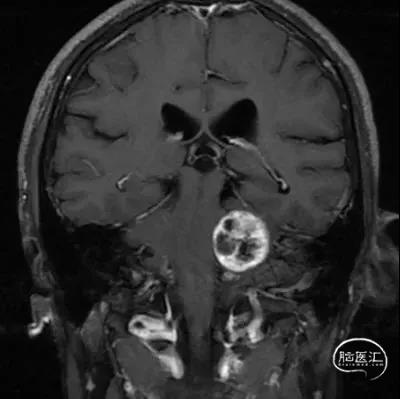

CASE 2 [ 左侧大型听神经瘤 ]

患者:男, 56y,左耳听力下降半年加重3月

肿瘤最大径约3.6cm

术前影像资料

扩大的内听道

该患者听神经瘤内听道口扩大很大,肿瘤在内听道内长入很深,肿瘤大部分是纤维结构,肿瘤质地很硬,血供很丰富和周围组织粘连很紧。为保护面神经功能,手术过程电生理经常报警,手术不得不经常停下来等待电生理监测波形恢复正常。术后面神经完整保留,手术历时4.5小时。